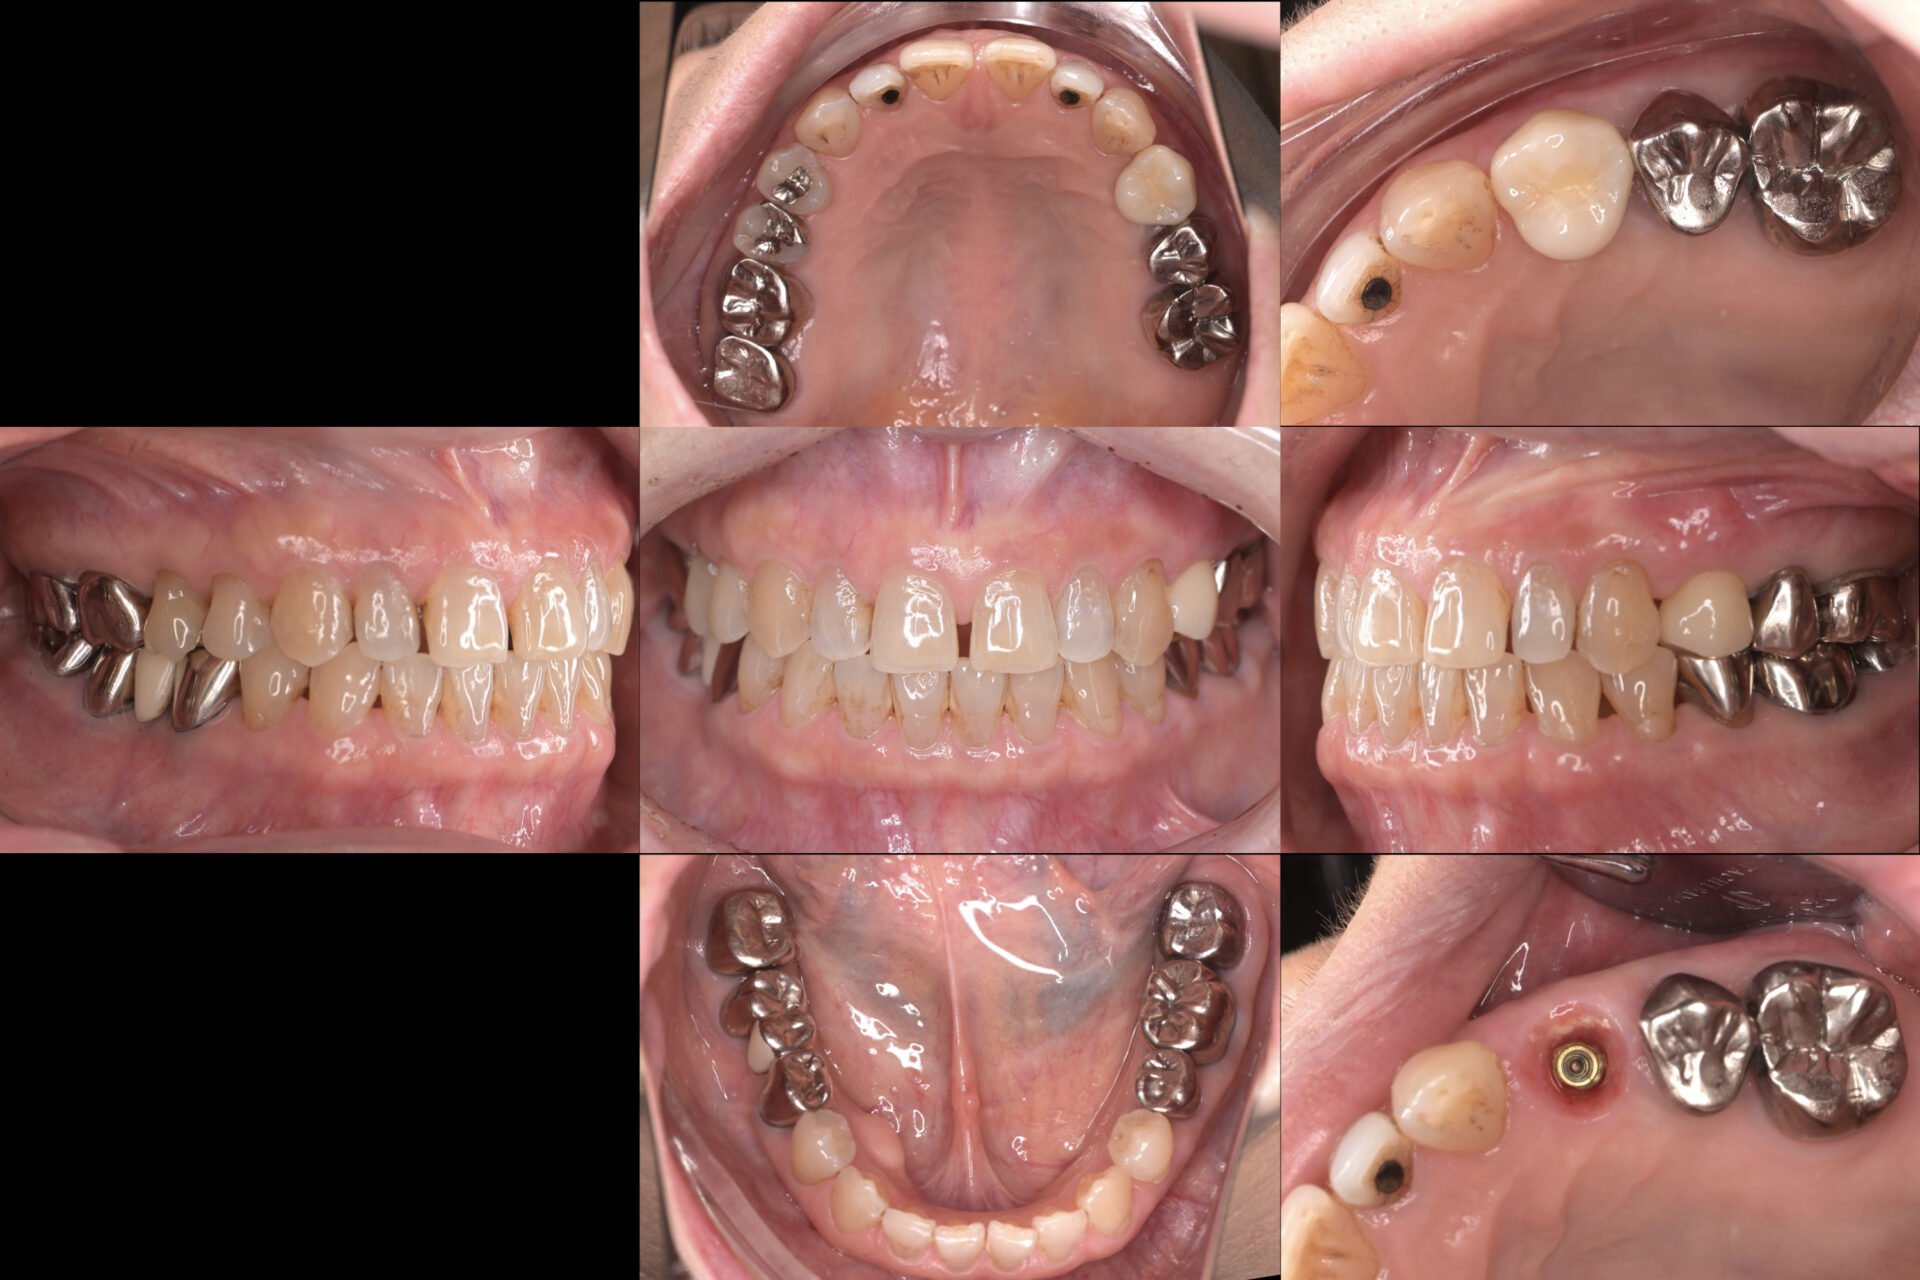

初診時と治療終了後

治療終了

治療後のメインテナンス

インプラント治療は、終了後のメインテナンスが非常に重要になります。

治療終了後も当院に3ヶ月に一回欠かさず受診してくださっています。

そのおかげもあり現在何一つトラブルが起きておらず、とても満足頂いております。